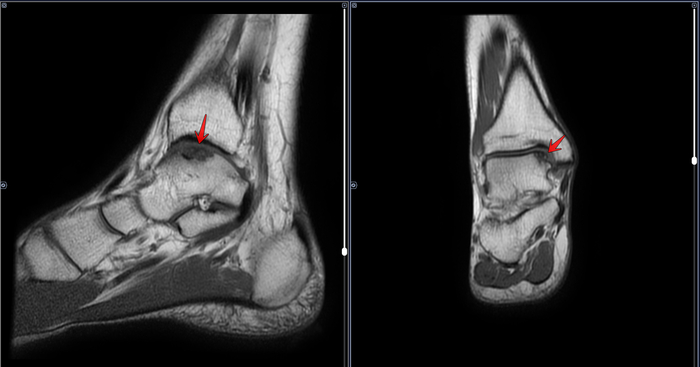

В анамнезе у призывника диагноз- дисплазия тазобедренных суставов, перенесенное оперативное лечение по поводу дисплазии в детстве. По данным рентгенографии костей таза: ШДУ справа 143 град, слева 143 град, сужение суставной щели справа до 3 мм, слева до 3.1 мм, остеофиты по верхне-наружным краям суставных щелей, шейка правой бедренной кости укорочена ,перекос таза вправо. Двусторонние участки разряжения костной ткани в межвертельной области(более выраженно справа)-как следствие перенесенных оперативных вмешательств. Заключение: Coxa valga bilateralis как следствие дисплазии тазобедренных суставов. Вторичный двусторонний коксартроз 1ст.